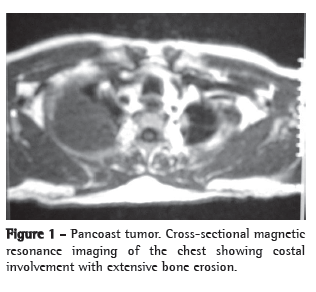

We report the case of a 49-year-old female patient, who worked as a maid in a rural area near the city of Dianópolis, Brazil. She presented a history of cough with purulent expectoration, which had intensified in the last four months. She also complained of unconfirmed fever and asthenia. She had received treatment for pneumonia with nonspecific antibiotic therapy in her town, however, with no clinical improvement. The patient reported having used a corticosteroid (prednisone), although not precisely reporting the reason, dose or duration of the treatment. She denied smoking, alcoholism, and was unaware of previous systemic diseases. Physical examination revealed good general health status, and pulmonary auscultation revealed the presence of crackling rales, mainly in the upper and posterior third of the right hemithorax. A high-resolution computed tomography scan of the chest, performed in November of 2006, showed consolidation in the anterior and posterior segments of the right upper lobe, with air bronchograms and interposed cavitation (Figure 1). In view of the clinical-radiological profile, she was submitted to a diagnostic fiberoptic bronchoscopy, which revealed purulent fluid within the tracheobronchial tree and an exophytic lesion with an irregular surface and yellowish color obstructing the bronchial lumen of the left lower lobe within the upper segment (Figure 2). The results of the biopsy of that lesion and the transbronchial biopsy of the posterior segment of the right upper lobe bronchus revealed the presence of septate hyphae with 45º dichotomous ramification, which are characteristic of Aspergillus sp. Direct testing and culture for acid-fast bacilli (Löwenstein-Jensen) and fungi (Sabouraud) of the bronchial lavage and bronchial brush samples were negative. No neoplastic cells were observed in this material. Blood workup, biochemical analysis and immunoglobulin levels were normal. Serology for HIV was negative. Based on the clinical, radiological and histopathological findings, a diagnosis of CNPA was made. Treatment was initiated with 200 mg/day of itraconazole, and significant clinical improvement was observed after twelve months of treatment.

A control high-­resolution computed tomography scan, performed in December of 2007, revealed total regression of the consolidation and cavitation in the right upper lobe, only residual parenchymal bands, translating to parenchymal scars, remaining (Figure 3).